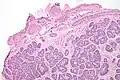

| Micrograph of a Sertoli cell nodule. H&E stain. | |

A Sertoli cell nodule is a benign proliferation of Sertoli cells that arises in association with cryptorchidism (undescended testis).[1] They are not composed of a clonal cell population, i.e. neoplastic; thus, technically, they should not be called an adenoma.[2]

Sertoli cell nodules are unencapsulated nodules that consist of:[2][3][4]

- cells arranged in well-formed tubules (that vaguely resemble immature Sertoli cells), with

- bland hyperchromatic oval/round nuclei that are stratified, and

- may contain eosinophilic (hyaline) blob in lumen (centre).

Micrograph of a Sertoli cell nodule. H&E stain.

Micrograph of a Sertoli cell nodule. H&E stain. -

Micrograph of a Sertoli cell nodule. H&E stain.

Micrograph of a Sertoli cell nodule. H&E stain.